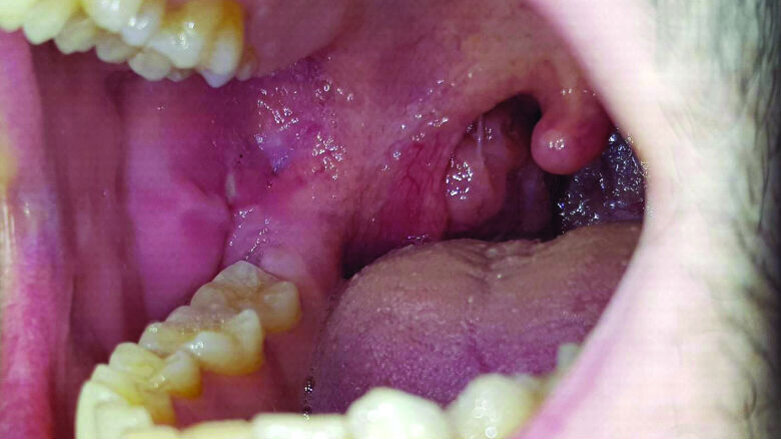

Un paziente maschio di 17 anni, in perfetto stato di salute generale, durante un controllo ortodontico presenta una lesione ulcerativa provocata dallo strofinamento della mucosa buccale con i bracket in corrispondenza del dente n 43-44-45 . Anche in questo caso si prescrive lo stesso collutorio puro per 1 minuto ogni 8 ore per 7 giorni e lo stesso gel orale, descritto precedentemente ogni 8 ore per 7 giorni. Dopo 5 giorni la lesione ulcerativa da strofinamento della mucosa buccale è completamente regredita (Figg. 3, 4).

Fig. 3 - Lesioni ulcerative provocate dallo strofinamento della mucosa buccale con i bracket in corrispondenza dei denti 43-44-45.

Fig. 4 - La lesione provocata dallo strofinamento della mucosa buccale con i bracket in corrispondenza degli elementi 43-44-45 è completamente regredita dopo 5 giorni di trattamento.